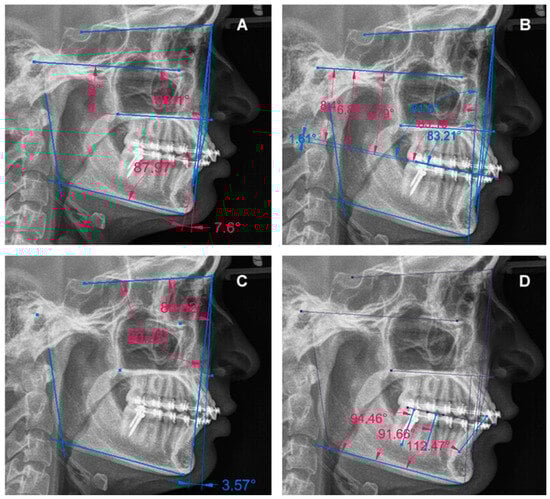

| Case | Skeletal Diagnosis | Distalization Arch | Time | COP | AOP | POP | I | 1M | 2M | SMP | VMP |

|---|---|---|---|---|---|---|---|---|---|---|---|

| 1 | Class I Neutral Angle | Mandible | T1–T2 | Flattened | Tipped | Flattened | Decreased | Increased | Decreased | Not changed | Not changed |

| T2–T3 | Tipped | Tipped | Flattened | Decreased | Decreased | Decreased | Not changed | Not changed | |||

| T1–T3 | Flattened | Tipped | Flattened | Decreased | Decreased | Decreased | Not changed | Not changed | |||

| 2 | Class I Low Angle | Mandible | T1–T2 | Tipped | Tipped | Flattened | Decreased | Decreased | Decreased | Not changed | Not changed |

| T1–T3 | Tipped | Tipped | Flattened | Decreased | Decreased | Decreased | Not changed | Not changed | |||

| 3 | Class II Neutral Angle | Maxilla | T1–T2 | Flattened | Flattened | Flattened | Increased | Decreased | Increased | Not changed | Not changed |

| T2–T3 | Tipped | Tipped | Tipped | Decreased | Decreased | Decreased | Changed | Not changed | |||

| T1–T3 | Tipped | Tipped | Flattened | Decreased | Decreased | Decreased | Changed | Not changed | |||

| 4 | Class II Low Angle | Mandible | T1–T2 | Flattened | Flattened | Flattened | Increased | Increased | Increased | Not changed | Not changed |

| T2–T3 | Tipped | Tipped | Tipped | Decreased | Decreased | Decreased | Not changed | Not changed | |||

| T1–T3 | Tipped | Flattened | Flattened | Increased | Decreased | Decreased | Not changed | Not changed | |||

| 5 | Class II Low Angle | Mandible | T1–T2 | Tipped | Tipped | Flattened | Increased | Decreased | Decreased | Not changed | Not changed |

| T2–T3 | Flattened | Flattened | Tipped | Decreased | Decreased | Increased | Not changed | Not changed | |||

| 6 | Class III High Angle | Maxilla | T1–T2 | Flattened | Flattened | Flattened | Increased | Decreased | Decreased | Not changed | Not changed |

| T2–T3 | Flattened | Flattened | Tipped | Decreased | Increased | Decreased | Not changed | Not changed | |||

| T1–T3 | Flattened | Flattened | Flattened | Decreased | Decreased | Increased | Not changed | Not changed | |||

| 7 | Class III High Angle | Mandible | T1–T2 | Flattened | Flattened | Tipped | Decreased | Decreased | Decreased | Not changed | Not changed |

| T2–T3 | Tipped | Tipped | Flattened | Decreased | Increased | Decreased | Not changed | Not changed | |||

| 8 | Class III High Angle | Mandible | T1–T2 | Tipped | Flattened | Flattened | Decreased | Increased | Increased | Not changed | Not changed |

| T2–T3 | Flattened | Tipped | Flattened | Increased | Decreased | Increased | Not changed | Not changed | |||

| T1–T3 | Tipped | Flattened | Flattened | Decreased | Decreased | Decreased | Not changed | Not changed | |||

| 9 | Class III High Angle | Maxilla | T1–T2 | Tipped | Tipped | Flattened | Decreased | Increased | Increased | Not changed | Not changed |

| T2–T3 | Flattened | Tipped | Flattened | Decreased | Decreased | Decreased | Not changed | Not changed | |||

| T1–T3 | Tipped | Tipped | Flattened | Decreased | Increased | Increased | Not changed | Not changed |